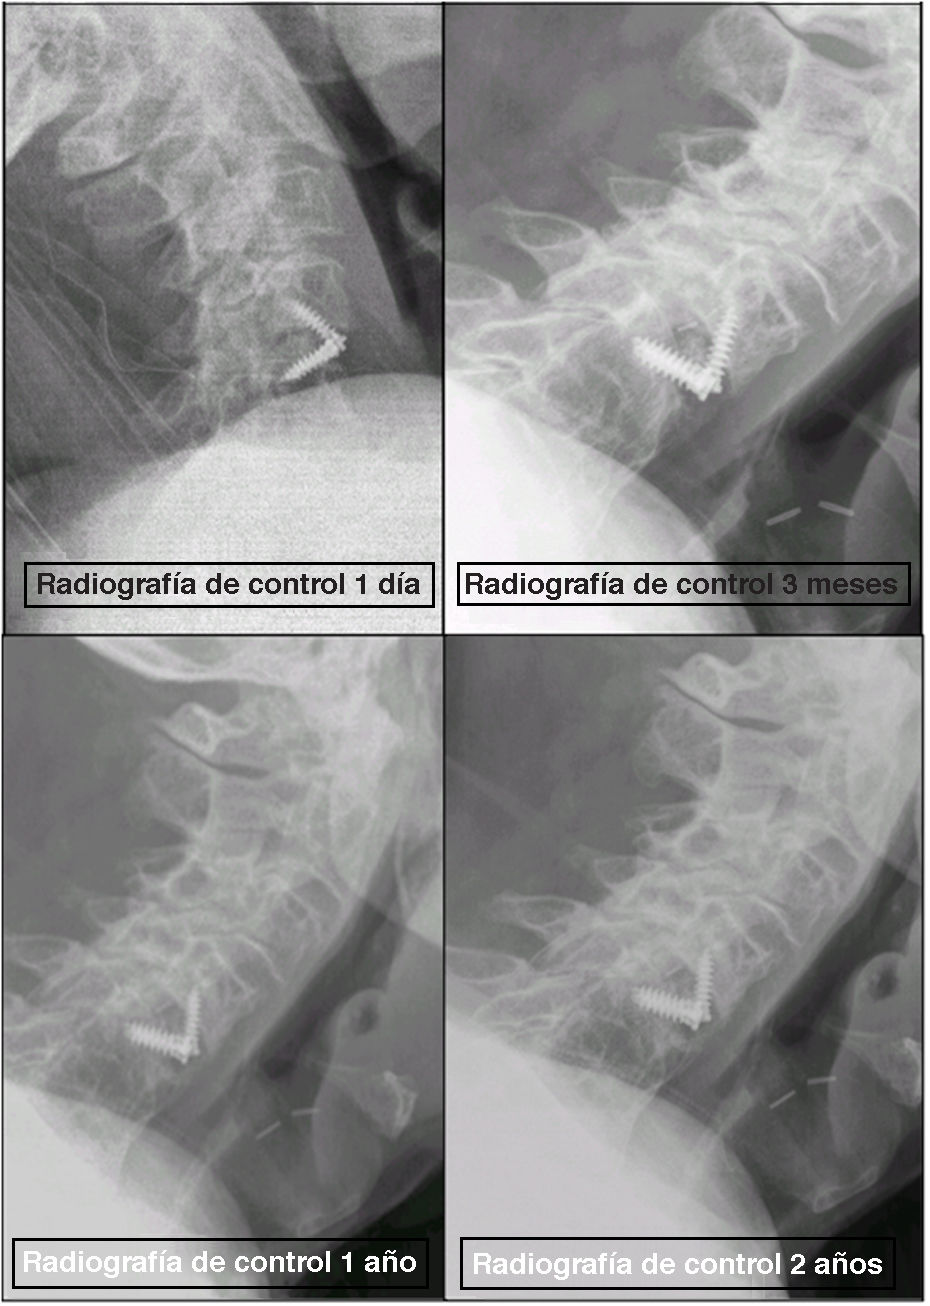

Se identificó un único caso de hundimiento (caso 35) a los 3 meses. El paciente permaneció asintomático, y el segmento progresó a fusión sólida en uno o 2años sin intervención quirúrgica (fig. 8).

Caso 35: hundimiento de la jaula con progresión benigna a fusión sólida. (A) Radiografía lateral al primer día postoperatorio. (B) Radiografía a los 3 meses que muestra hundimiento en la placa terminal superior. (C) Radiografía al año que muestra una consolidación progresiva. (D) Radiografía a los 2años que confirma una fusión sólida y el mantenimiento de la alineación sin necesidad de cirugía de revisión.